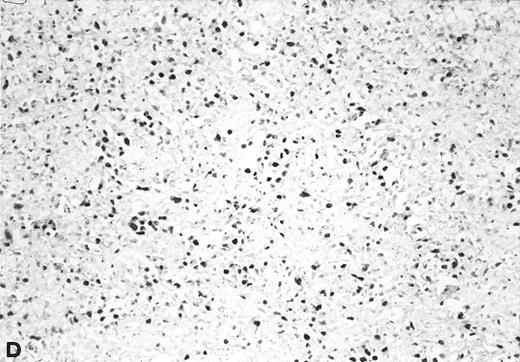

The relative amount of EBV DNA in the EBV+ samples was estimated by comparing the OD values of their amplified EBNA2 products to the OD values obtained using standard reference samples, as detailed in Materials and Methods. As shown in Table 3, most of the EBV+ lymphadenopathy samples had very low levels of EBV DNA (ie, scored either 1+ or 2+) and accordingly, none of the analyzed lymphadenopathy specimens was found to be EBV+ by Southern blot analysis. Three cases were analyzed by in situ hybridization with EBER probes; 1 (no. 20) showed viral sequences in 2% to 3% of cells (Fig 3), and 2 (nos. 21 and 23) were negative. Interestingly, in 4 of 6 coinfected lymphadenopathy cases, the amounts of type 1 and type 2 EBV DNA were equivalent, while either type 1 or 2 predominated in the 2 remaining cases (Table 3).

In situ hybridization with EBER probes. In a representative lymphadenopathy case (no. 20), rare EBER+ cells are seen, mainly in the interfollicular areas (A and B). In a representative lymphoma case (no. 46) nearly half of the cells are EBER+ (C and D). Original magnification: ×130 (A and C) and ×260 (B and D).

Twelve of the 16 EBV+ lymphoma samples scored from 3+ to 6+ for EBV DNA content (ie, 102- to 105-fold higher than that found in the majority of the lymphadenopathy samples), and most were also positive by Southern blot analysis (Table 4). Seven of 11 tested samples were also positive for viral sequences by in situ hybridization with EBER probes (Table 4). Although the high content of EBV in these tumors strongly indicated that they arose from the proliferation of EBV+ cells, 4 large cell lymphomas contained consistently low levels of EBV DNA, a finding that might reflect either a dilution effect by nonneoplastic EBV− cells in the analyzed samples, or the presence of few infiltrating reactive EBV+ B cells.